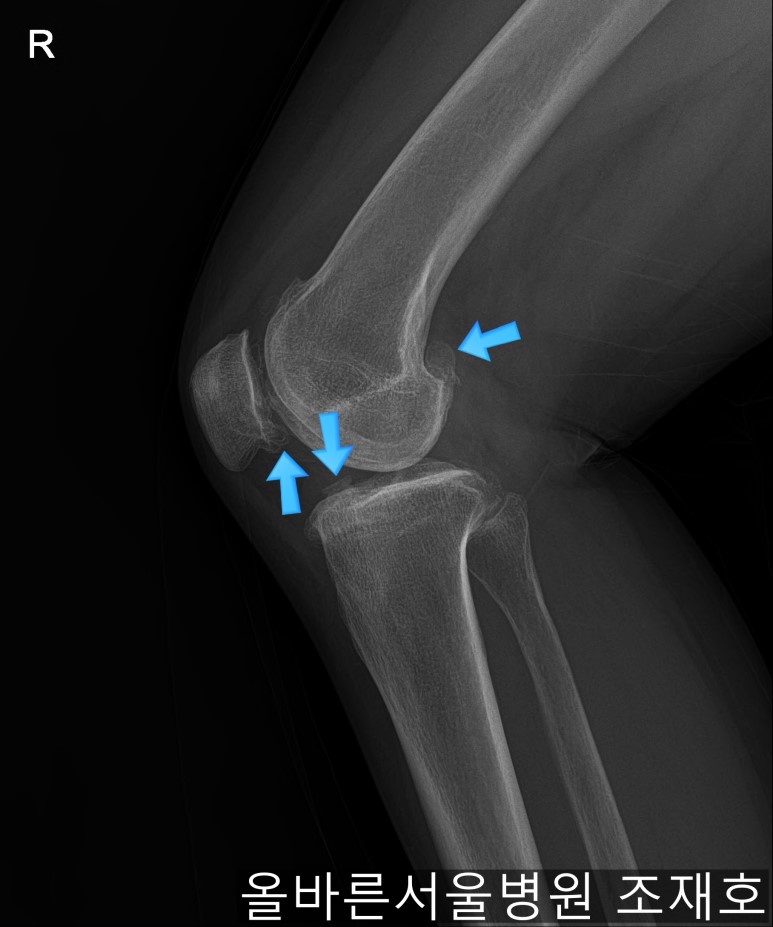

通过观察侧位片子可看到:由于关节炎已经长出骨刺。髌骨关节有炎症。

虽然有髌骨关节炎,但软骨损伤不算严重。